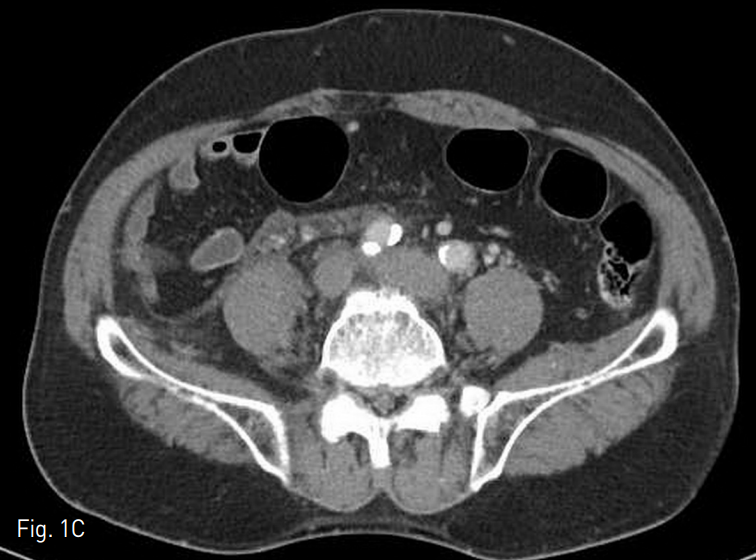

복부 전산화 단층촬영에서 간내부와 간하부의 하대정맥을 따라서 광범위한 혈전이 관찰되었고 양측 신 정맥과 장골정맥까지 혈전증이 동반되어 있었음 (Fig. 1).

Fig. 1

Diffuse thromobosis are in intrahepatic IVC (A), left renal vein (B), and both iliac veins (C)